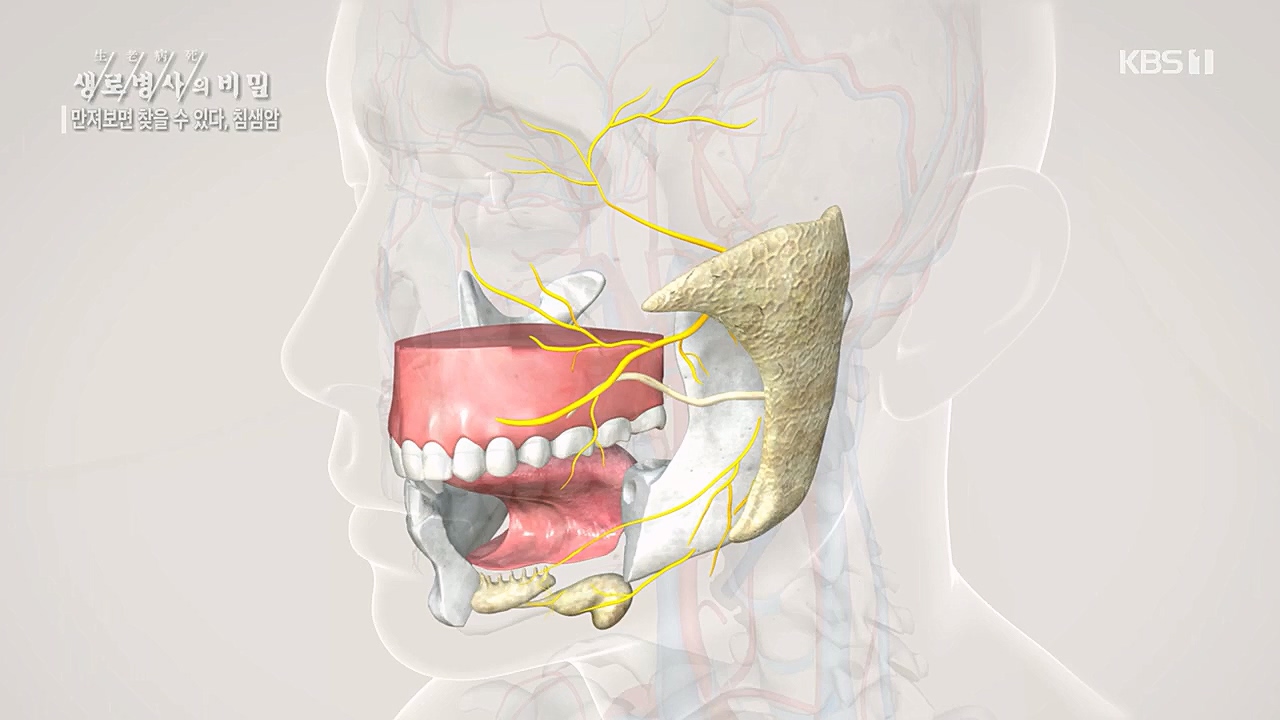

만져보면 찾을 수 있다 침샘암

선양성암인데, 그 특징이 상당히 천천히 자라고요

일반적으로 분비되는 물질에는 산도

악하선(턱밑샘)에서 나오는 침과는 성분이 좀 다릅니다